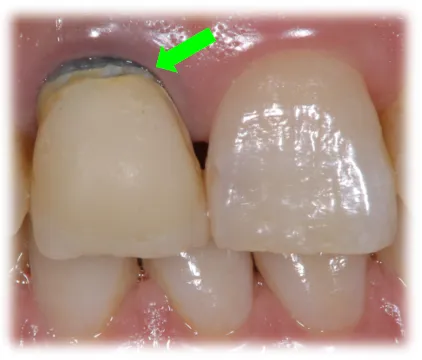

被せ物を外すと根が真っ黒に変色しています。

-

古い銀合金の土台が使用されていました。これが錆びて、

金属イオンが根に染み付いて変色していました。

残念ながら根に染み付いた金属イオンは完全には取れません。

●銀合金の土台を外して、樹脂製ファイバーの土台に変更

●歯の強度を失わないように、可能な限り変色部を取り除く

●歯茎のきわは歯茎の厚みが薄く、根の色を透過してしまうので、なるべく根の方までセラミックでカバーする

このような治療を行うことで、歯茎の黒ずみはほとんどわからなくなり、被せ物もセラミックで作り直すことで、患者様のご希望通りの自然な見た目を実現することができました。